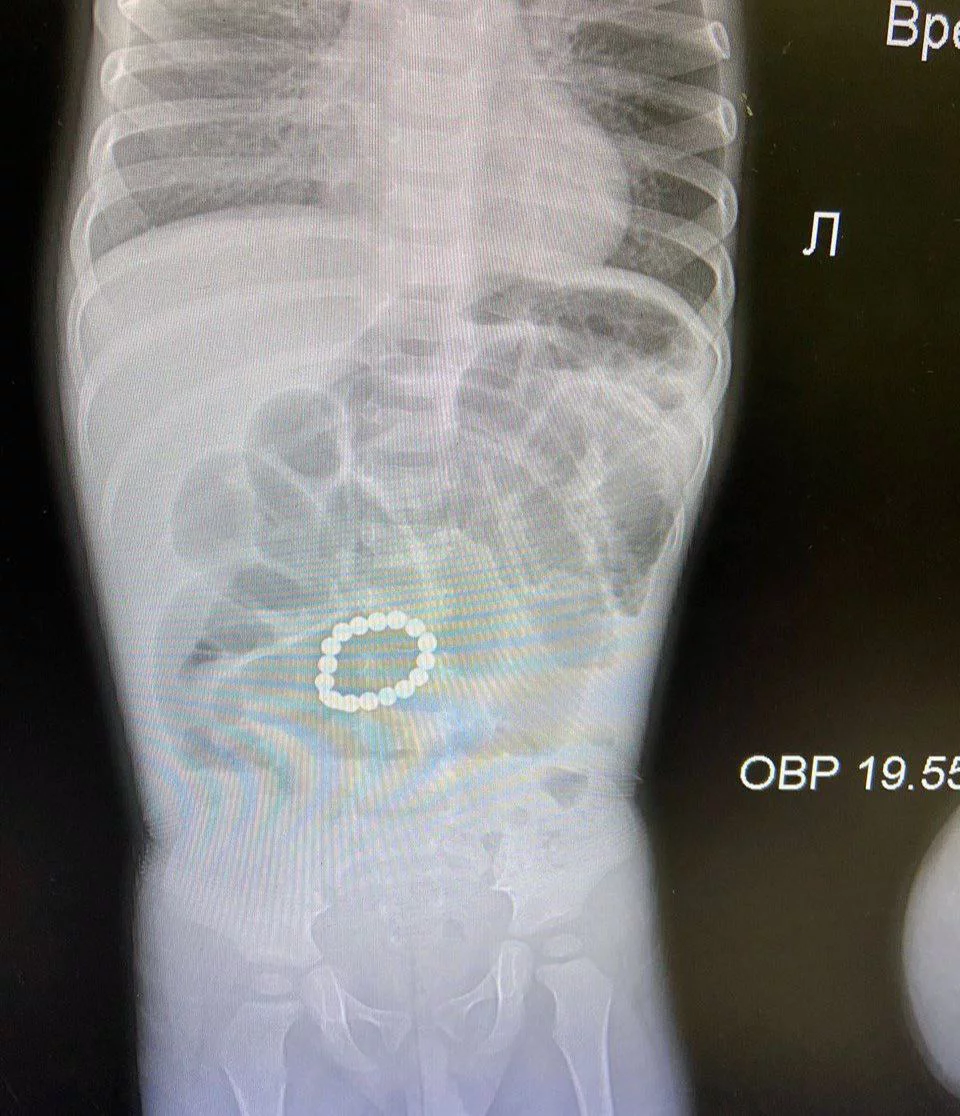

Магнитные шарики на рентгене: Интересные находки

Раздел: Картинки на заметку